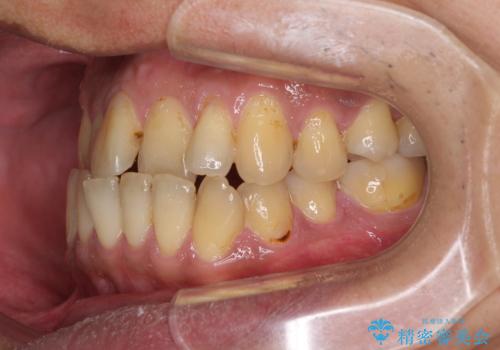

前歯のクロスバイトを改善 ワイヤー装置での非抜歯矯正

- 骨格的な咬み合わせのズレ、前歯のデコボコとクロスバイトを気にして来院された患者様です。

骨格のズレが顕著であると診断され、マウスピース矯正では奥歯の咬み合わせが整えにくいと判断し、ワイヤー装置による矯正治療を行うこととしました。

上下の叢生は速やかに改善できましたが、右側のクロスバイトの改善に1年以上の期間を要しました。